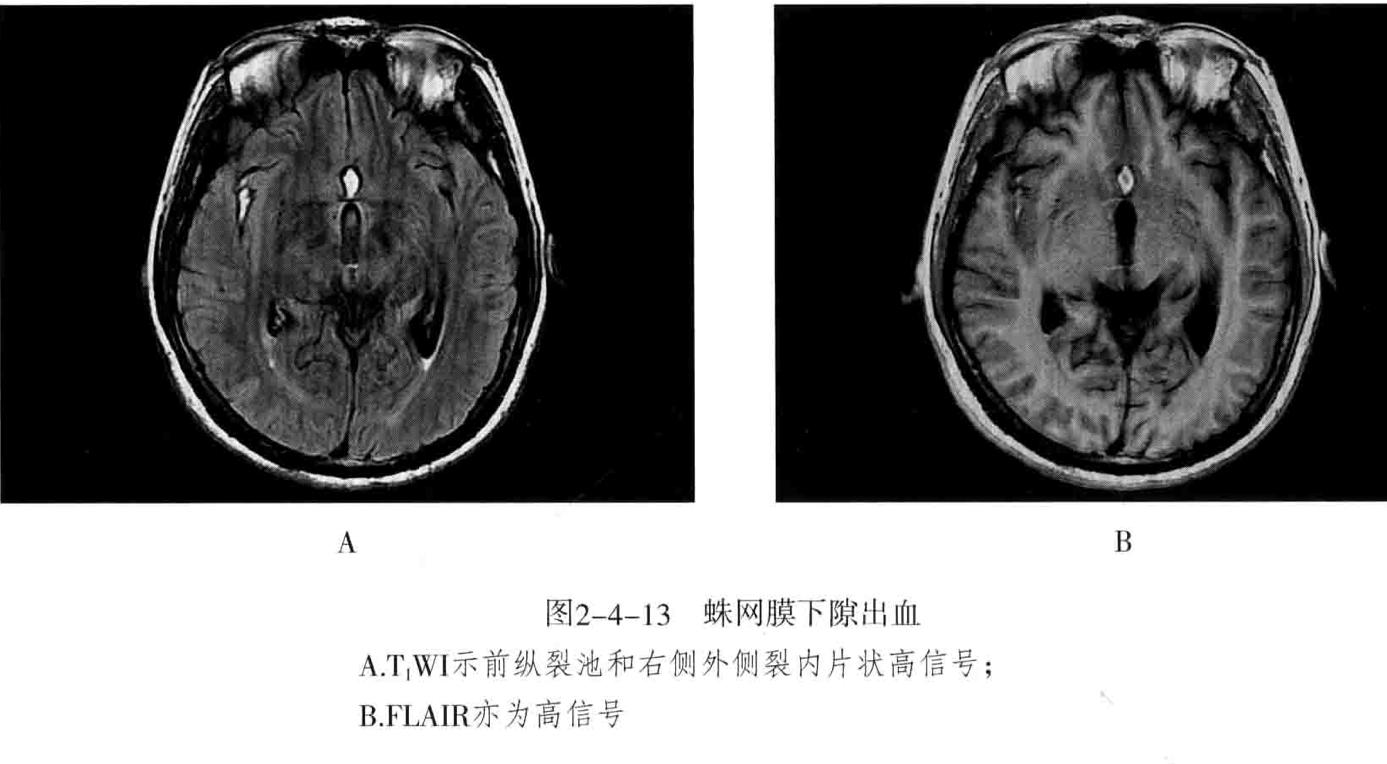

七、蛛网膜下腔出血:颅内血管破裂后血液流入蛛网膜下隙

1. 分外伤性和非外伤性,非外伤性包括——颅内动脉瘤(最常见病因)、高血压动脉硬化和颅内血管畸形等导致血管破裂引起。

2. 影像表现:CT:大脑镰、小脑幕密度增高,脑沟、脑裂内线样高密度影

3. MRI:急性期不敏感,以FLAIR显示较佳,呈高信号;亚急性期表现为蛛网膜下隙内局灶性信号异常,FLAIR、T1WI、T2WI均为高信号。慢性期在T2WI上出现低信号为特征。